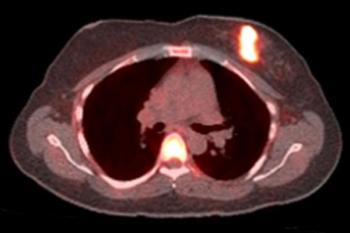

A low-dose CT for lung cancer screening can also predict a five-year cardiovascular disease risk of death when using a deep learning algorithm.

Hormone therapy is only effective in roughly half of estrogen receptor-positive cancers. Being able to identify patients that will not respond could save valuable treatment time.